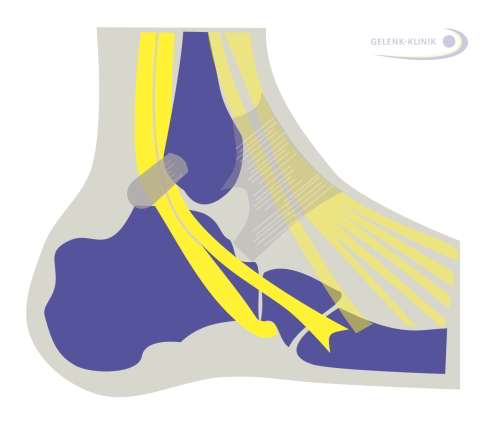

Brennende oder stechende, und manchmal dumpfe Schmerzen auf der Oberfläche des Sprunggelenks resultieren häufig aus Nerveneinklemmungen. Man spricht auch von einem Nervenkompressionssyndrom. Die unter der Haut verlaufenden Nerven werden in ihrem Verlauf gequetscht oder gedrückt. Häufig sind die horizontal am Sprunggelenk verlaufenden Bänder, die den Tarsaltunnel bilden, für diese Schmerzen verantwortlich. Der Tarsaltunnel bildet eine eingeengte Durchtrittsstelle für Nerven und Blutgefäße am Sprunggelenk. Man spricht daher vom Tarsaltunnelsyndrom. Dabei bildet jedes Band eine eigene mögliche Druckstelle. Häufig entstehen diese Nervenschmerzen am Sprunggelenk nach Schwellungen im Gewebe. Verschiedene Ursachen können diese Schwellung auslösen: Wassereinlagerungen (Ödeme) können ebenso die Ursache sein wie eine Verletzung mit einer lokalen Schwellung. Neben brennenden Schmerzen begleitet häufig auch ein Taubheitsgefühl an der Fußsohle das Tarsaltunnelsyndrom.

Schematische Darstellung des Tarsaltunnels an der Außenseite des Sprunggelenks. Alle Sehnen, Nerven und Blutgefäße, die vom Unterschenkel in das Bein hineinlaufen, passieren diesen Tarsaltunnel. Eine Schwellung im Sprunggelenk führt daher zu schmerzhaften Nerveneinklemmungen. © Dr. Thomas Schneider